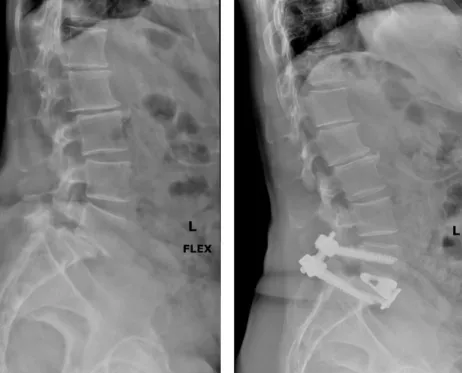

椎間融合手術:在受損的椎體之間放置植入物,使它們更加穩定。

骨折或移位:植入物移位、脫落或植入物與骨折不穩定導致骨折或移位。

矯形不良:出現脊柱彎曲、扭曲或不對稱的情況,影響患者的姿勢和外觀。